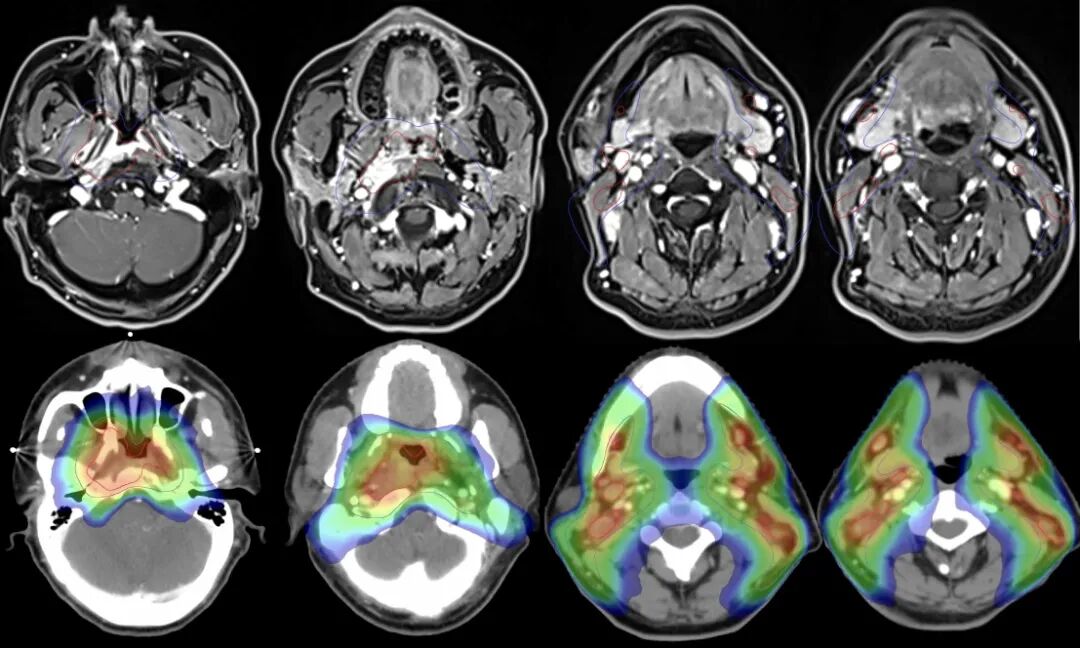

病例3:44歲男性患者,耳悶,涕中帶血起病,并可觸及雙側(cè)頸部腫物。為局部晚期鼻咽癌,伴多發(fā)雙側(cè)頸部淋巴結(jié)轉(zhuǎn)移。

圖注:治療前后比對(duì)。上排為治療前,可見鼻咽腫物主要位于右側(cè)鼻咽部,局部侵犯非常嚴(yán)重,造成右側(cè)頭長肌完成受侵,并侵犯斜坡及寰椎骨質(zhì);雙側(cè)頸動(dòng)脈鞘區(qū)多發(fā)淋巴結(jié)轉(zhuǎn)移。下排為治療后,鼻咽腫塊基本完全消失,受侵肌肉基本恢復(fù);多發(fā)淋巴結(jié)轉(zhuǎn)移基本完全縮退。

病例4:48歲男性患者,耳悶及頸部腫物起病。磁共振檢查可見雙側(cè)鼻咽頂部腫物,向后侵犯斜坡骨皮質(zhì);雙側(cè)頸部多發(fā)轉(zhuǎn)移腫大淋巴結(jié),為局部晚期鼻咽癌。

圖注:治療前后比對(duì)。上排為治療前,可見鼻咽腫物向前侵及翼突,向后累及斜坡;側(cè)咽后間隙及雙側(cè)頸部多發(fā)腫大淋巴結(jié)。下排為治療后,鼻咽區(qū)腫瘤病灶完全消失,頸部轉(zhuǎn)移淋巴結(jié)基本消失。